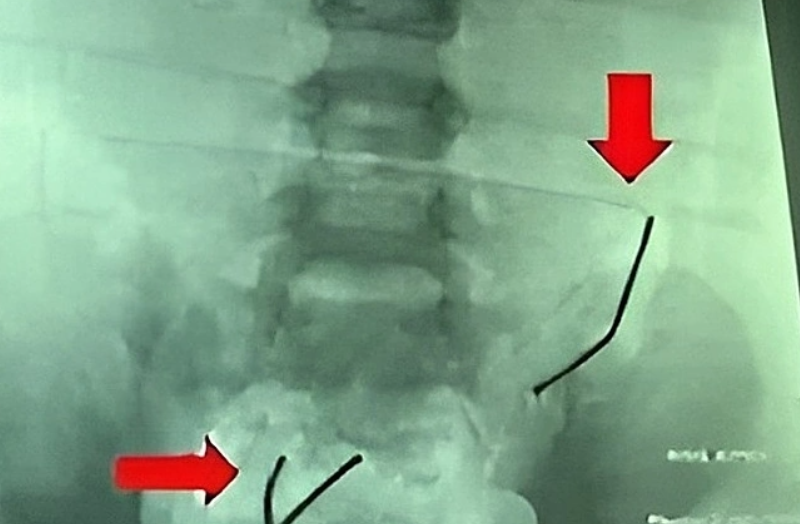

베트남에서 한 5세 남아가 장난감에서 나온 작은 자석을 삼켜 소장에 구멍이 8개나 뚫려 수술받은 사연이 전해졌다. 병원 제공

3일(현지시간) VN익스프레스에 따르면 A(5)군은 3일간 복통과 구토 증상을 보여 부모와 함께 병원을 찾았다. 엑스레이(X-Ray) 검사 결과 소장에서 자석 두 가닥이 확인됐고, 초음파에서 장염과 복막염 소견이 나타났다.

의료진은 긴급 복강경 수술을 통해 지름 2~3㎜ 크기의 소장 천공 8곳을 확인하고, 원인으로 추정되는 작은 자석 20개를 꺼냈다. 해당 자석은 녹이 슬어 장 점막에 심각한 손상을 입힌 상태였다.

당시 23개월 B군을 키우는 보호자는 B군이 자석 장난감을 손에 쥔 채로 캑캑거리는 모습을 보고 병원을 찾았다. 의료진은 B군의 복부 엑스레이와 컴퓨터단층촬영(CT) 검사로 소장 안쪽에 여러 개의 자석이 엉켜있는 모습을 확인했다.